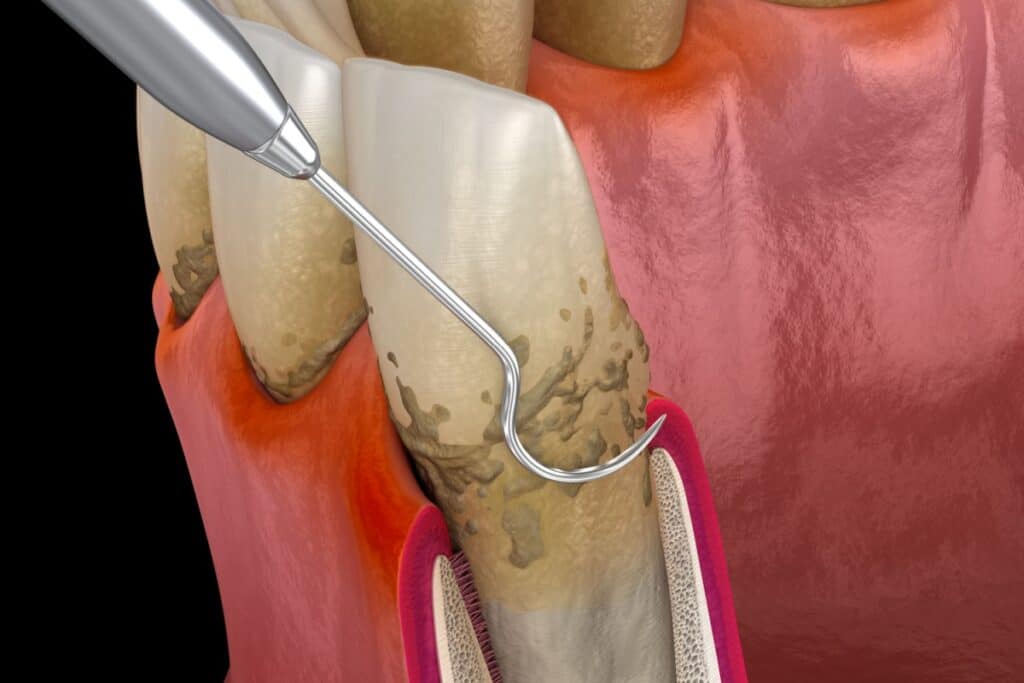

Root planing becomes necessary when bacteria and tartar have moved below your gum line, creating pockets where your toothbrush and floss cannot reach. This deeper cleaning addresses the root cause of gum disease before it progresses to more serious stages.

A healthy pocket depth around your teeth typically ranges from 1 to 3 millimetres. Depths of 4 millimetres or more often indicate the need for root planing treatment.

The root planing procedure goes much deeper than a regular cleaning. Your dental team works below the gum line to remove bacteria and tartar from tooth roots, areas you cannot see or clean at home.

A dentist can use thin probes to measure the space between your tooth and gum, looking for areas where bacteria might be hiding below the surface. Healthy gums fit snugly around your teeth with shallow pockets. Deeper measurements could indicate areas that need deep scaling and root planing treatment to remove bacteria and tartar buildup.

X-rays can also show your dental team what is happening below the gum line. Combined with visual examination, these tools help determine whether you need an additional scaling and root planing session.